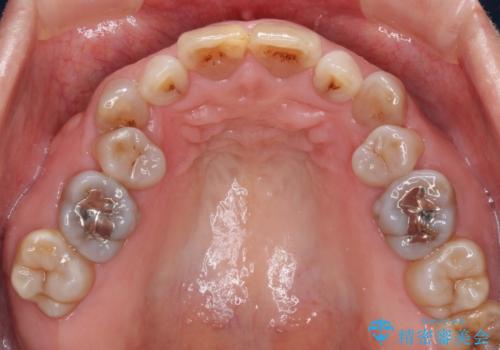

- 小さいころからの歯の変色と矯正治療の後戻りを気にして来院された患者様です。

気になる変色歯を仮歯に変え、その後歯列不正を矯正治療で改善し、最後にオールセラミッククラウンにて補綴治療することとしました。